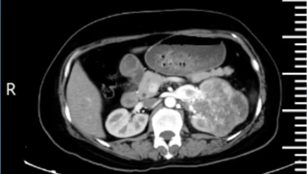

近日,我院泌尿外科在学科带头人陈善群主任的带领下,成功为一位 56 岁的女性患者施行了后腹腔镜下左肾癌根治性切除手术。此次手术的成功,解除了恶性肿瘤对患者生命的严重威胁,充分展现出泌尿外科在重大疾病诊疗以及高难度手术方面的诊疗能力。

2、手术成功,患者预后良好

(术后病理提示)